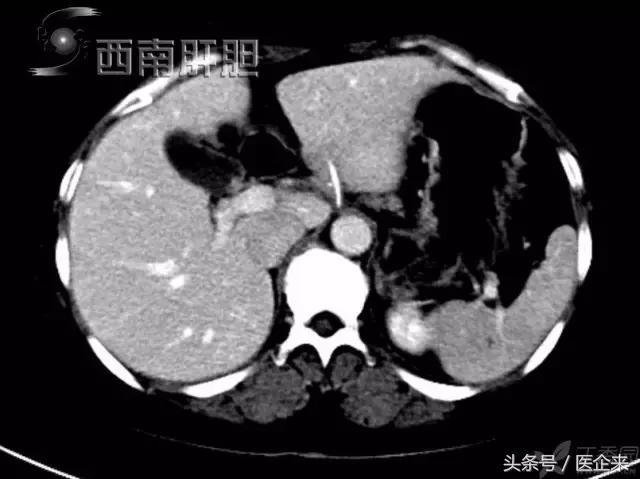

9.不慎吞入的鱼刺刺破了胃部,进入肝脏(小小的鱼刺*伤杀**力巨大...)

腔镜下取出异物,证实为鱼刺